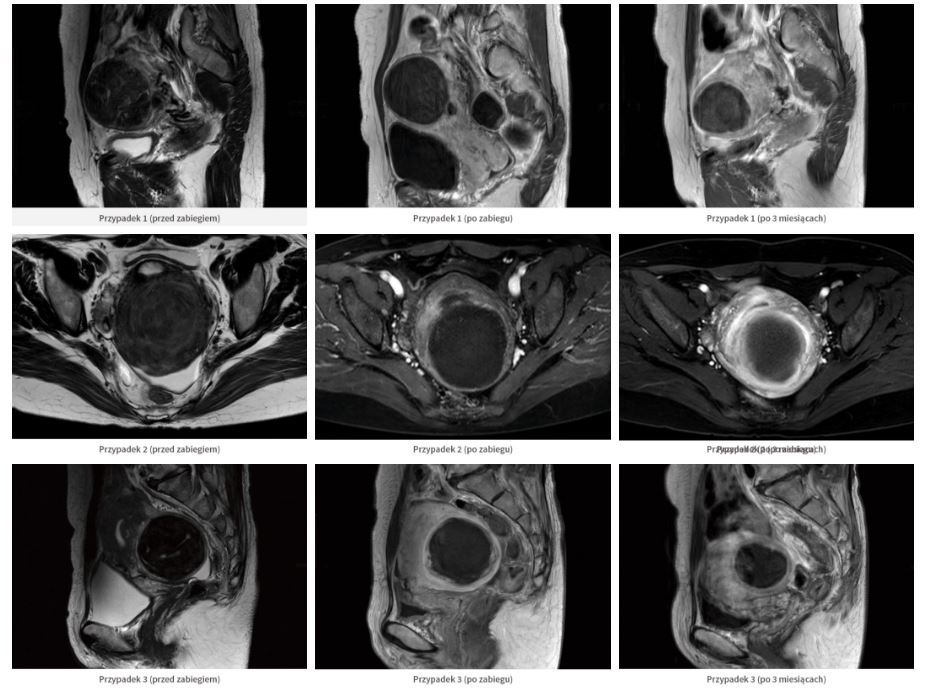

Alpinion HIFU ALPIUS 900 to najwyższej klasy urządzenie do leczenia mięśniaków macicy działające pod kontrolą USG, które wykorzystuje wiązkę ultradźwiękowa wysokiej intensywności HIFU (FUS).

HIFU Alpinion ALPIUS 900 to innowacyjna, niespotykana dotąd metoda leczeniu mięśniaków macicy z wykorzystanie technologii HIFU pod kontrola USG. System gwarantuje bezpieczne i szybkie leczenie mięśniaków bez ryzyka związanego ze standardowym zabiegiem chirurgicznym.  ALPIUS 900 nie wymaga instalacji rezonansu magnetycznego do przeprowadzenia terapii.

HIFU jest zabiegiem całkowicie bezpiecznym, nieinwazyjnym, minimalizującym ból (w trakcie i po zabiegu) oraz przyjmowanie środków farmakologicznych oraz przede wszystkim wysoka skuteczność.